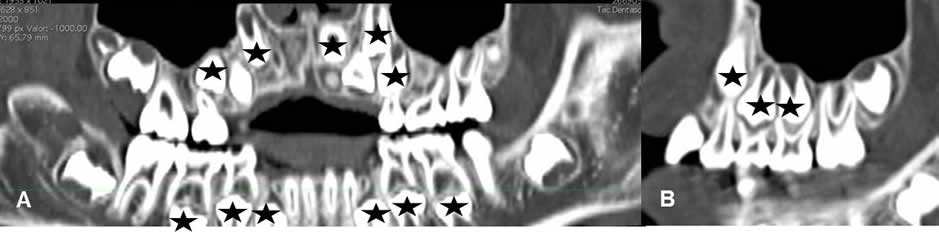

Fig 1. Dentición primaria.

A: TAC reconstrucción coronal y B: TAC reconstrucción sagital. Los dientes permanentes se identifican en el interior del maxilar y la mandíbula. (Estrellas). Estos van migrando gradualmente cuando se caen los primarios, hasta ocupar su posición usual.